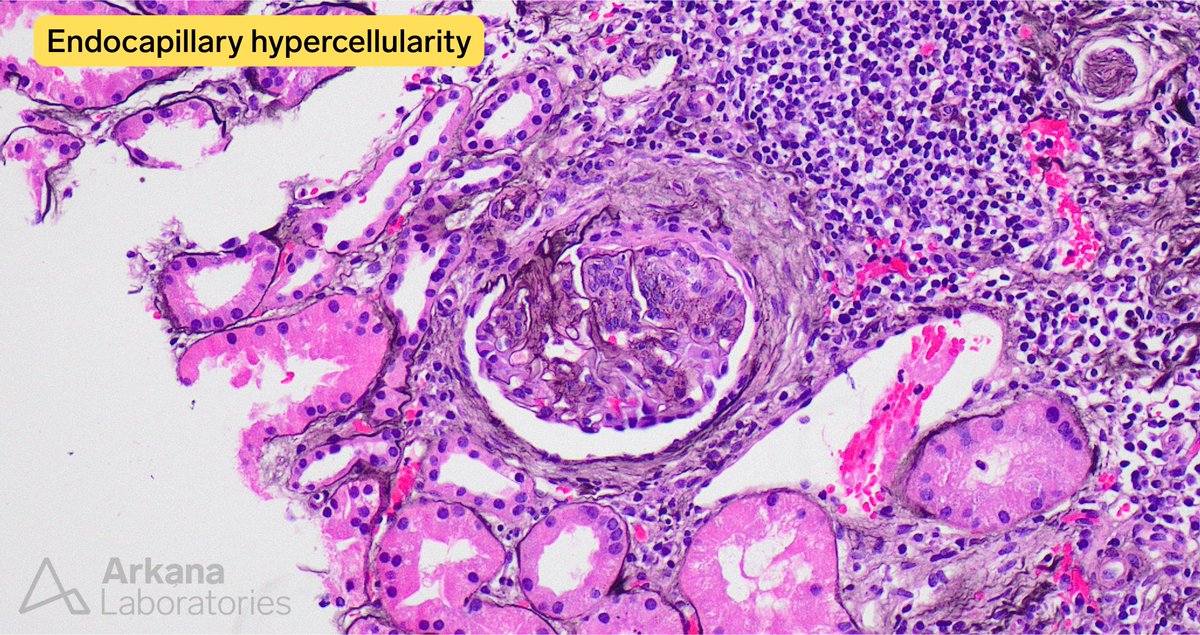

Disappearing glomeruli: loss of linear IgG in anti-GBM nephritis